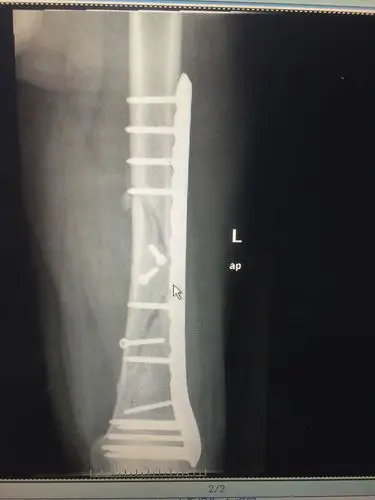

股骨远端骨折后愈合再次骨折治疗{图片}请指点

右股骨多段粉碎性骨折